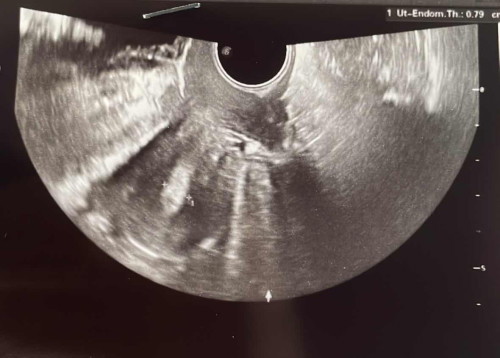

Saya test minggu lepas naik macam ni . Terus pergi scan . Tapi doktor cakap tak nampak apa lagi . Normal atau tak eh ? Sebelum pergi scan doktor tanya last period bila , last period 18/4 tapi 1/7 ada turun darah macam spotting . Scan rahim pun doktor cakap rahim nipis 🥲

Doktor cakap mungkin yg 1/7 tu period tapi sikit . So kalau betul 1/7 tu period maksudnya baru nak masuk 4w